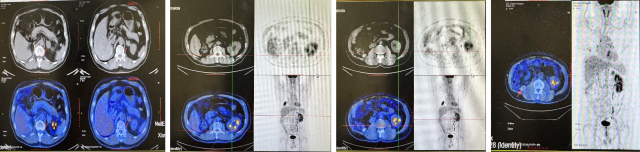

CT:1. 右肾癌伴右肾静脉受累,侧支循环形成;2. 右肾上腺结合部结节灶,转移可能;3. 右输尿管上段管壁局部增厚:侵犯?4. 左肾囊肿。

PETCT:1. 右肾中-下份混合密度软组织肿块,糖代谢轻度升高,SUVmax6.4, 右肾内糖代谢稍增高灶,SUVmax3.8,右肾癌合并肾静脉瘤栓形成;2. 右肾上腺结合部低密度灶,糖代谢轻度增高,转移瘤,SUVmax3.1。

PETCT(2022.10):1. 左侧肾上腺结节灶,糖代谢增高,转移瘤可能性大;2. 左肾多发结节状突起,糖代谢增高,考虑转移瘤,需结合增强 CT 综合判断;3. 右下肺切除术后,术区未见复发;4. 右侧胸壁局部增厚、糖代谢增高,术后改变?建议追踪。